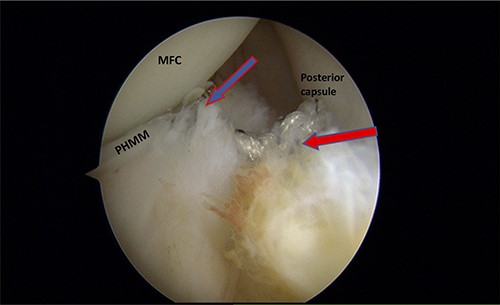

A posteromedial portal was utilized to repair both ramp tears using all-inside sutures, and curved suture hooks were inserted through the posteromedial portal. The first tear was repaired, and a non-absorbable suture was passed between the peripheral edge of the PHMM and attachment of the meniscotibial ligament (Fig. 6). The second tear was then repaired by passing the suture through the posterior capsular tissue, creating a bridge between the two tears to restore the meniscocapsular attachment (Fig. 7).

Trans-notch view of the posteromedial compartment of the left knee showing the surgical repair of the first tear. The blue arrow indicates the first lesion at the meniscosynovial junction in the red-red zone area. The red arrow shows the second tear at the meniscocapsular attachment. PHMM, posterior horn of the medial meniscus; MFC, medial femoral condyle